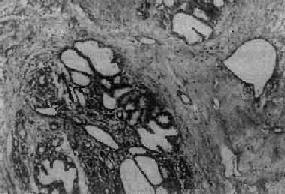

图13-24 纤维腺病 末梢导管、腺泡和间质均呈明显增生,部分腺泡及导管扩张,间质内有一些淋巴细胞浸润 (三)囊肿病 乳腺囊肿病(cystic disease)以小叶末梢导管和腺泡高度扩张成囊为特征。囊腔大小不等,多少不一,往往在肉眼上即可见到多人散在分布的小囊腔,直径在500~700μm以上者,称为囊肿病。镜检,囊内衬立方或柱状上皮及肌上皮细胞,在早期尚可见两层细胞结构,以后,部分或全部呈萎缩状态;有时在上皮萎缩消失处可见溃疡或肉芽组织形成;有的囊肿上皮则可增生,上皮细胞呈柱状,体积增大,有时增生的上皮构成筛状;或呈多发性乳头状瘤样增生,当若干扩张的导管和囊肿内均有乳头状增生时,则称为乳头状瘤病。此外,往往可见上皮呈大汗腺化生,细胞体积大、胞浆丰富、嗜酸性,PAS反应阳性。这种大汗腺化生往往是良性的标志,不要误诊为癌。 现在一般认为腺病与癌的关系不大,囊肿病伴有增生性病变时,癌变的机会较多,属于癌前病变。